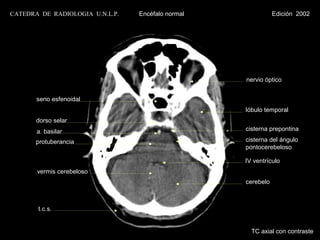

CATEDRA DE RADIOLOGIA U.N.L.P.   Encéfalo normal              Edición 2002

seno esfenoidal

lóbulo temporal

dorso selar

a. basilar                                  cisterna prepontina

protuberancia                               cisterna del ángulo

pontocerebeloso

IV ventrículo

vermis cerebeloso

cerebelo

t.c.s.

TC axial con contraste